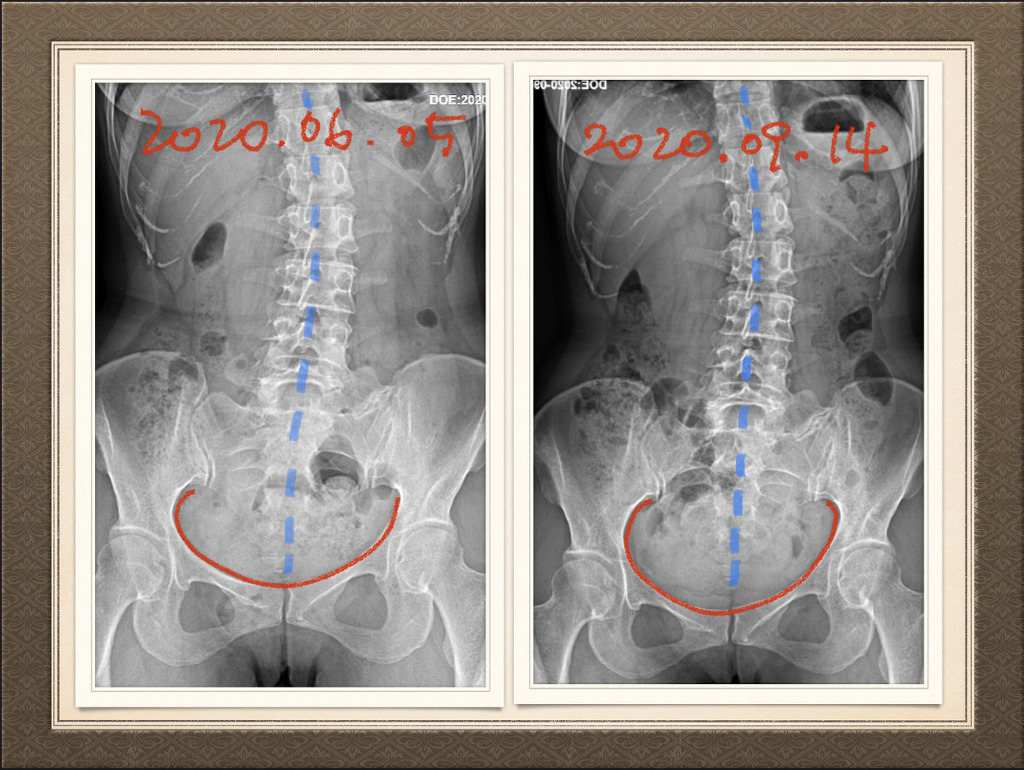

6/5과 9/14 본원에서의 3번자세 측정과 변화

100일 수련,나름 열심히 해왔다고 생각했기에,그리고 스스로 체감하고 있는 점도 있어 기대하며 병원에 갔는데 엑스레이 비교 검토해주시는 의사분이 거의 변화가 없으니 어디 불편하면 다시 오라고 하셔서,실망한 마음으로 본원으로 와서 엑스레이 제출하고 사후측정.

옷갈아입고 나가려는데 경지혜 선생님과 이희진 선생님이 다급하게 부르셔서 컴퓨터실로 갔더니,저의 전후 엑스레이를 판독해주시며 "전문가가 아니더라도 한눈에 알아보시겠죠!!골반의 상태가 많이 좋아졌어요~"라고.병원에서 실망하고 돌아온 저에게 어쩜~~100일의 노력이 결실 맺어지는 듯한 순간이었습니다.선생님들 감사합니다~~ 판독해주시지 않았더라면 체험사례에 올려지지 못했을 사진입니다.지금 글을 작성하며 다시 체크해보니 골반뿐 아니라 휘어진 척추도 살짝 펴져가고 있었습니다!!